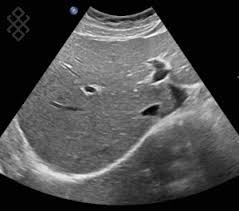

L’Échographie utilise des ultrasons (ondes sonores à haute fréquence) pour visualiser en temps réel les organes, les vaisseaux et les tissus mous du corps. C’est un examen non invasif, indolore et qui n’utilise pas de rayons ionisants. L’Écho-Doppler est un complément indispensable qui mesure la direction et la vitesse de la circulation sanguine (flux).

Exploration des organes intra-abdominaux (foie, vésicule biliaire, pancréas, rate, etc.).

Exploration de l'arbre urinaire, de la vessie et de la prostate.

Exploration des organes pelviens chez l'adulte (vessie, utérus, ovaire, prostate).